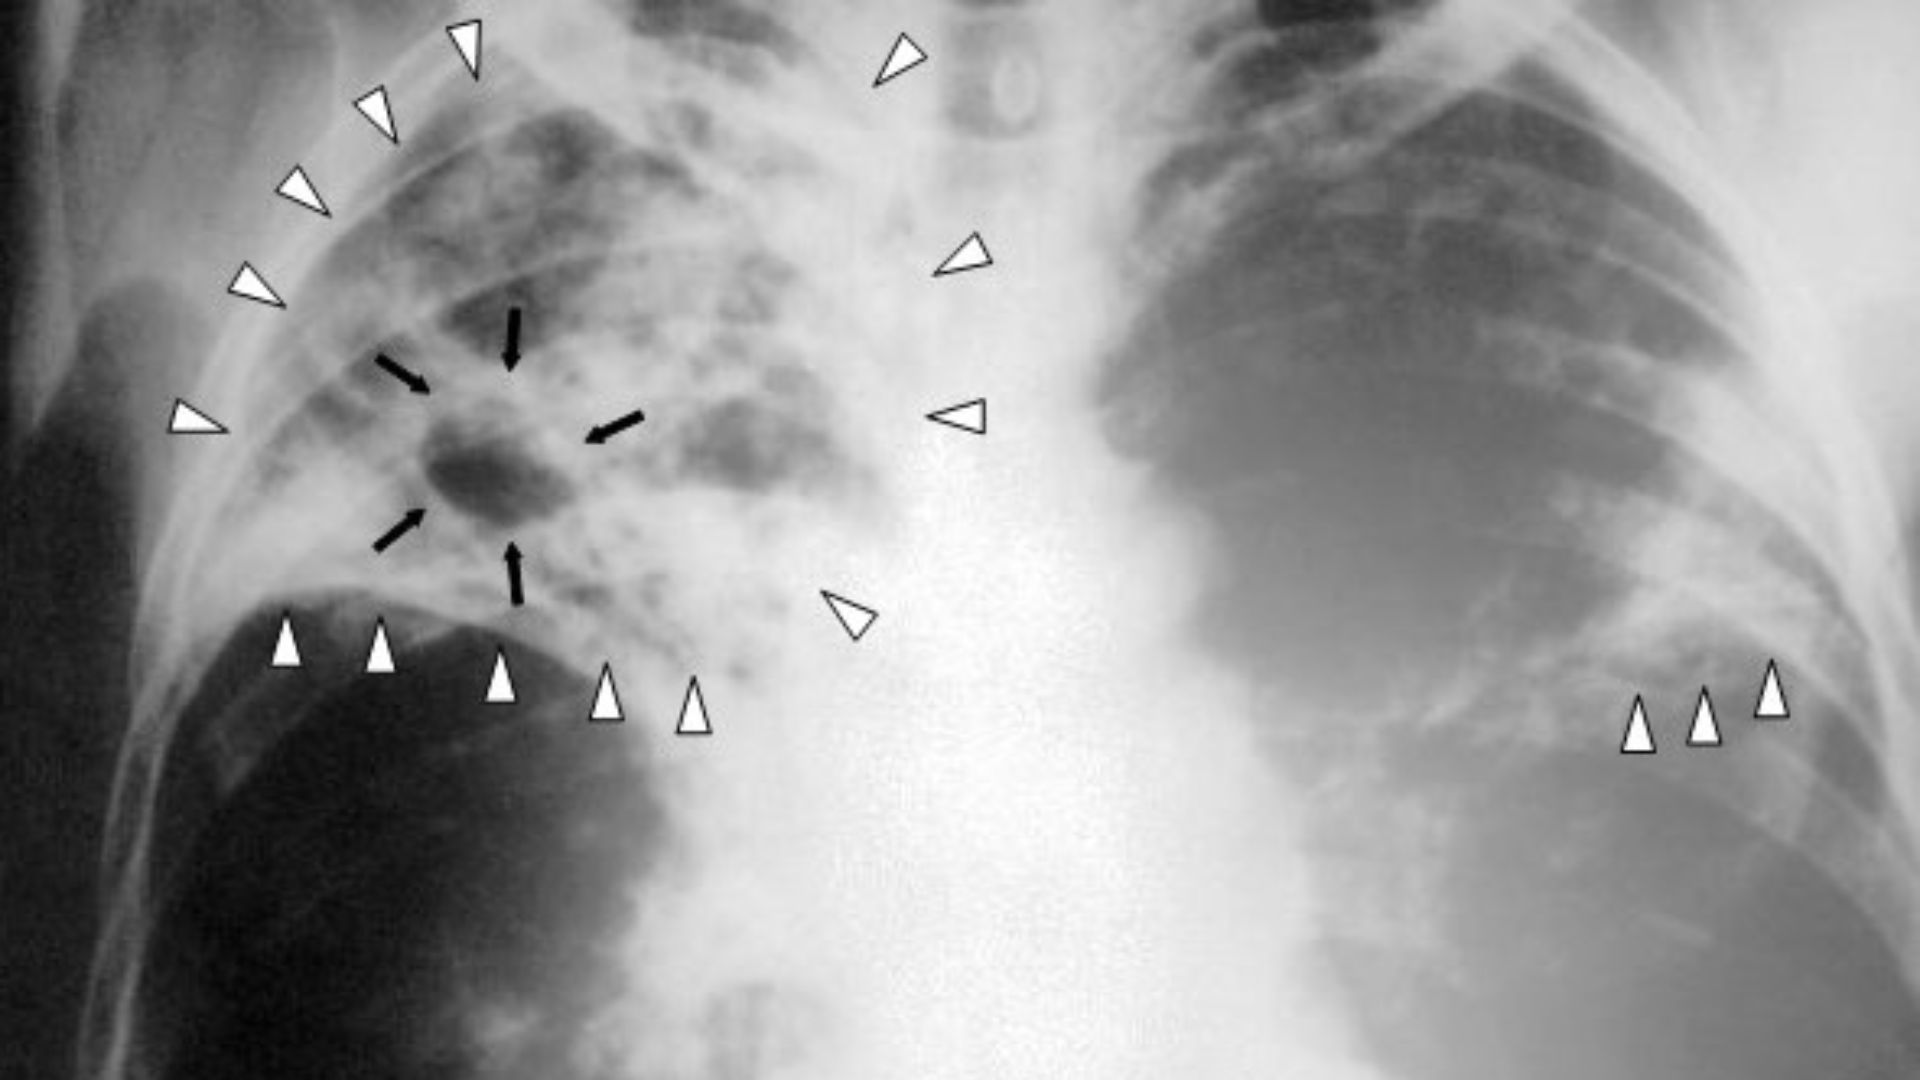

3. The Third Plague Pandemic

Starting in the late 19th century, plague traveled with global shipping and colonial trade networks, striking port cities and then radiating inland. In places like India, the death toll reached into the millions, and the response hardened modern ideas about surveillance, quarantine authority, and urban sanitation.